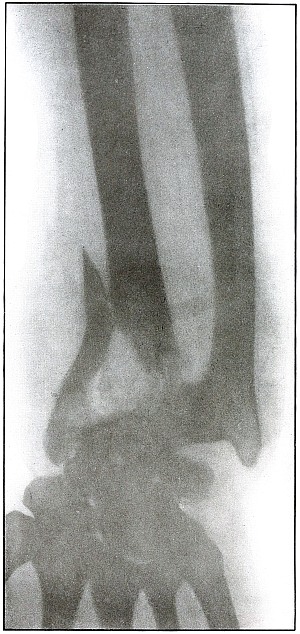

Rifle—Plate 17.

UPPER EXTREMITY.

Gunshot Fracture of the Elbow.

The bullet in transverse course and high velocity through both bones of the forearm struck the head of the radius, thus starting several splitting lines of fracture and separating large fragments. Smaller fragments which received some of the energy of the missile have been carried along with it in turn, striking the ulna and carrying away smaller fragments from it and causing the laceration which marks the wound of exit.

Such wounds, with laceration of soft parts and fragmentation of the bone, are prone to infection, against which treatment is directed. The indications to be met are much like those of the wound shown in plates 18 and 19. Excision or immediate methods of bone repair are contraindicated by infection.

Results will depend upon the nature and extent of infection. [Pg 46]